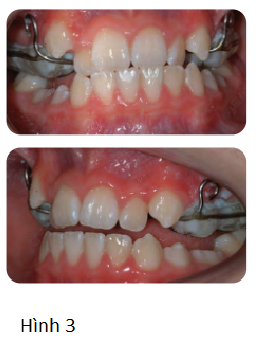

Bệnh nhân nam 10 tuổi tới phòng khám nha khoa vì không thích vị trí của răng nanh hàm trên và khớp cắn. Không có tiền sử y khoa liên quan. Bệnh nhân có sai lệch khớp cắn hạng III với kiểu xương hạng III trung bình, chiều cao tầng mặt dưới trung bình, mức độ chen chúc nặng, R25 mọc ngầm và cắn chéo răng cửa mà không có trượt chức năng trên cung răng hỗn hợp giai đoạn cuối. (Hình 1)